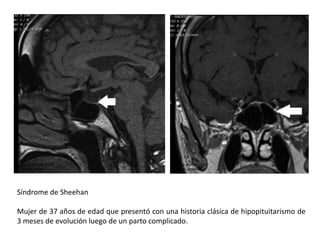

Síndrome de Sheehan

Mujer de 37 años de edad que presentó con una historia clásica de hipopituitarismo de

3 meses de evolución luego de un parto complicado.

Síndrome de Sheehan Mujerde 37 años de edad que presentó con una historia clásica de hipopituitarismo de 3 meses de evolución luego de un parto complicado.